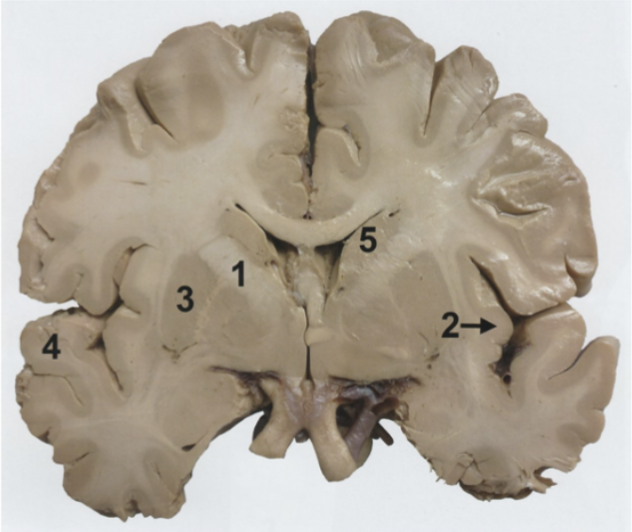

Vilken siffra markerar capsula interna? (1p)